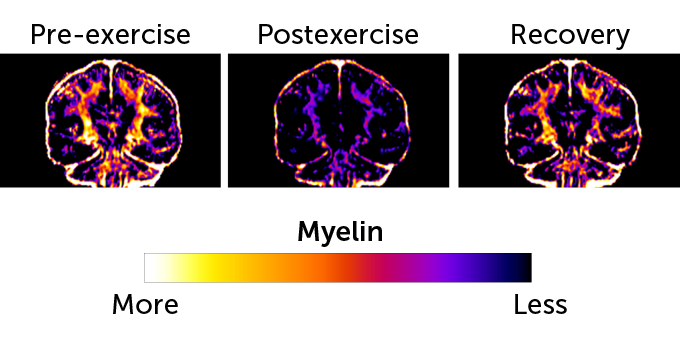

Long-distance runners may tap into myelin as a fuel source for the brain. The fatty tissue insulates nerve cells and seems to diminish just after a race, then build back up in the following weeks.

Marathon runners appear to rely on myelin, the fatty tissue bundled around nerve fibers, for energy during a race, scientists report October 10 in a paper posted at bioRxiv.org. In the day or two following a marathon, this tissue seems to dwindle drastically, brain scans of runners reveal. Two weeks after the race, the brain fat bounces back to nearly prerace levels. The find suggests that the athletes burn so much energy running that they need to tap into a new fuel supply to keep the brain operating smoothly.

Using an MRI, his team scanned the brains of four marathon runners in the days before and after the race, and two of the runners two weeks later. A day or two after the race, the team saw a reduction in the amount of myelin in the brain. That suggested the myelin wrapped around nerve fibers had thinned, Matute says. After two weeks, much of the myelin had returned, thickening again around neural fibers.